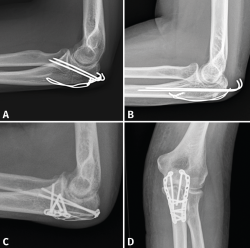

Figura 8. Ejemplos de fracturas de olécranon en 2 partes (tipo 2A) fijadas con obenque (A y B) y fracturas de tipo 2B fijadas con distintos diseños de placas (C y D).